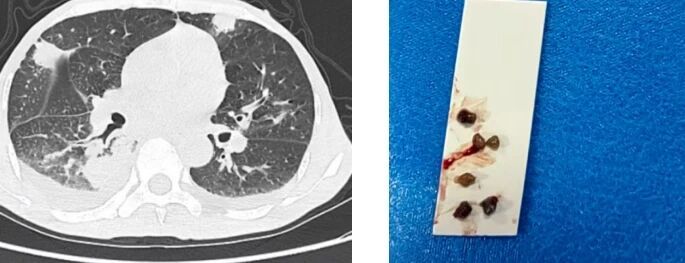

1月10日,思南县人民医院院呼吸与危重症医学科在浙江大学医学院附属邵逸夫医院呼吸与危重症医学科张冀松博士的指导下,首次完成“导航+超声(EBUS-GS)支气管镜下活检术”。该技术结合胸部CT影像通过导航路径的规划及r-EBUS的再次确认,精确锁定常规镜难以触及的肺外周病灶,然后将活检钳送入锁定位置,成功取到肺外周病灶,最终明确诊断。

患者何先生(化名),57岁,因“咳嗽、咳痰1月余”入院。既往有肝脾肿大病史,未系统诊治,平素饮食欠佳、贫血;胸部CT检查显示双肺外周多发性病灶,经抗感染治疗效果欠佳,入院完善相关检查,经全院讨论后,不排除淋巴瘤可能,建议进一步活检明确诊断;因患者消瘦、贫血,经皮肺穿刺活检术,气胸、出血风险较大,综合考虑后建议行”导航+超声(EBUS-GS)支气管镜下活检术”。

结合胸部CT影像通过导航路径的规划及r-EBUS的再次确认,成功取到肺外周病灶。